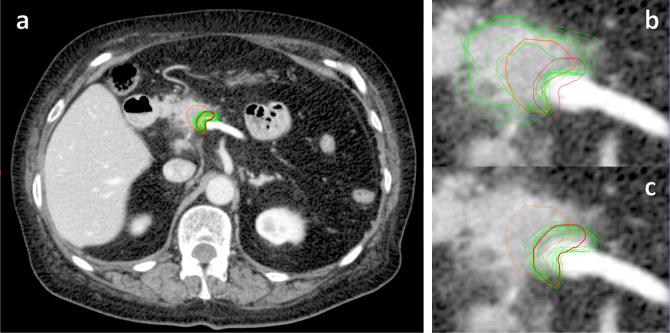

Reference and mean investigator volumes for GTV were 2.1 cm3 and 6.03 cm3 (95% CI 3.92–8.13 cm3) respectively, and for boost volume were 1.1 cm3 and 1.25 cm3 (1.02–1.48 cm3) (Fig. 2, Fig. 3). Mean Dice conformity coefficients for GTV and boost volume were 0.47 (0.38–0.56) and 0.61 (0.52–0.70), significantly higher for the boost volume (p = 0.01); mean discordance indices (DI) were 0.65 (0.56–0.75) and 0.39 (0.28–0.49), significantly lower for the boost volume (p = 0.001); mean Geographical Miss Indices (GMI) were 0.17 (0.10–0.23) and 0.33 (0.23–0.43), p = 0.005. Correlation coefficient for GTV volume with DI was 0.93 (0.65–0.99, p = < 0.001), and for GTV with GMI was −0.06 (−0.73–0.68, p = 0.899) (Fig. 4).

Fig. 2.

Reference (orange = GTV, red = boost volume) and investigator contours (green) of boost volume (images a and c) and GTV (image b) on contrast-enhanced axial CT of patient with borderline-resectable pancreatic carcinoma.